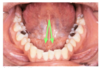

black = pyterygomandibular raphe

What connects the lips to the adjacent gum?

median labial frenulum